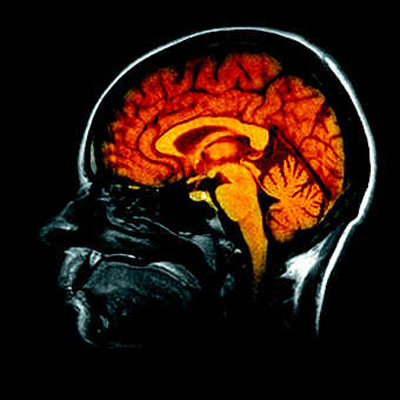

La mémoire est une activité biologique et psychique qui permet de retenir des expériences antérieurement vécues.